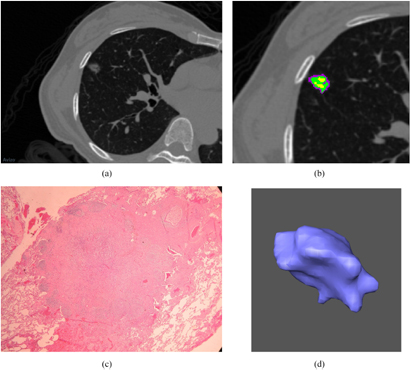

An open software package Imaging Biomarker Explorer (IBEX) was used in the nodule delineation and quantitative analysis of radiomics feature extraction from the thin-section CT images (Zhang et al 2015). Radiomics is an emerging research area in medical imaging for advanced image analysis in which quantitative features of tumor phenotypes are extracted from an imaging modality such as computed tomography, magnetic resonance imaging, or positron emission tomography (Kumar et al 2012, Lambin et al 2012, Aerts et al 2014, Zhang et al 2015). These phenotypic features include tumor shape, statistical distribution of gray-scale intensities, and texture properties (Kumar et al 2012, Lambin et al 2012, Aerts et al 2014, Zhang et al 2015). In our work using localized thin-section CT with radiomics feature extraction and machine learning, nodules were first manually delineated by an experienced research assistant on the image viewer of IBEX. Final nodule delineation was modified and approved by a radiologist whose expertise is in the lung cancer imaging. Two sets of images of a benign and malignant nodule acquired from the localized thin-section CT scan are shown in figures 2 and 3. Their corresponding pathological photographs and 3D views are also shown.

Figure 2. (a) A benign nodule is shown in a localized thin-section CT image. The window level is −500 HU and the window width is 1500 HU. A 49-year-old female has a benign pulmonary nodule in RML. The pathological diagnosis revealed the nodule is composed of fibrosis and pneumocyte hyperplasia due to chronic inflammation after CT-guided localization and wedge resection. (b) An enlarged image of figure 2(a). Different subregions within the benign nodule are identified by clustering pixels based on different CT densities. (c) A pathological photograph of this benign nodule is shown in figure 2(a). The microscopic view of the cellular scale is shown. (d) A 3D view of this benign nodule is shown in figure 2(a). The morphological view is shown by the computer graphic method of surface rendering.